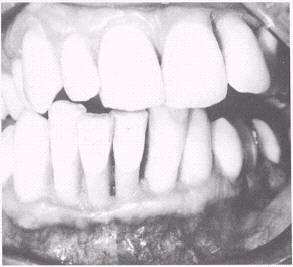

Acute Necrotizing Ulcerative Gingivitis

Acute necrotizing ulcerative gingivitis (ANUG) (fig. 5-8) is a disease commonly referred to as trenchmouth, or Vincent's infection. It is characterized during the acute stage by redness, swelling, pain, accumulation of calculus around the sulcus of the teeth, and bleeding of the gingival tissues. Usually there is a film of necrotic white or grayish tissue around the teeth. This membrane may be wiped off, leaving a raw, bleeding base. The ulceration of the gingival crest results in a characteristic punched-out appearance and loss of the interdental papillae. There is an unpleasant odor and a foul taste in the mouth. The gingival tissues bleed easily when touched, and patients will complain of not being able to brush their teeth or chew well because of the pain or discomfort.

Figure 5-8.\Acute necrotizing ulcerative gingivitis (ANUG).